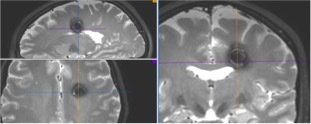

NEURONAVIGATION + IONM

Trans-sulcal Approach

Pre-operative

Post-operative